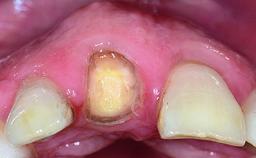

Replacement of an Upper Right Central Incisor with Root Resorption: Ridge Preservation, Delayed Placement of an NC Bone Level Roxolid Implant

A 32-year-old female Caucasian patient with a compromised maxillary right central incisor was referred to us by a general dentist. Her chief complaints were discomfort and mobility of tooth 11 with unsatisfactory esthetics due to discoloration. The patient reported a previous trauma, some years earlier, as the origin of pathology on the afflicted tooth. Anamnesis was negative for any other dental or periodontal pathology in the remaining dentition. The patient did not take any medication and reported to be a light smoker (5–10 cigs/day). She had high esthetic expectations of her treatment. The extraoral examination revealed a high smile line with full exposure of her maxillary teeth and surrounding soft tissue in the area between the second premolars.